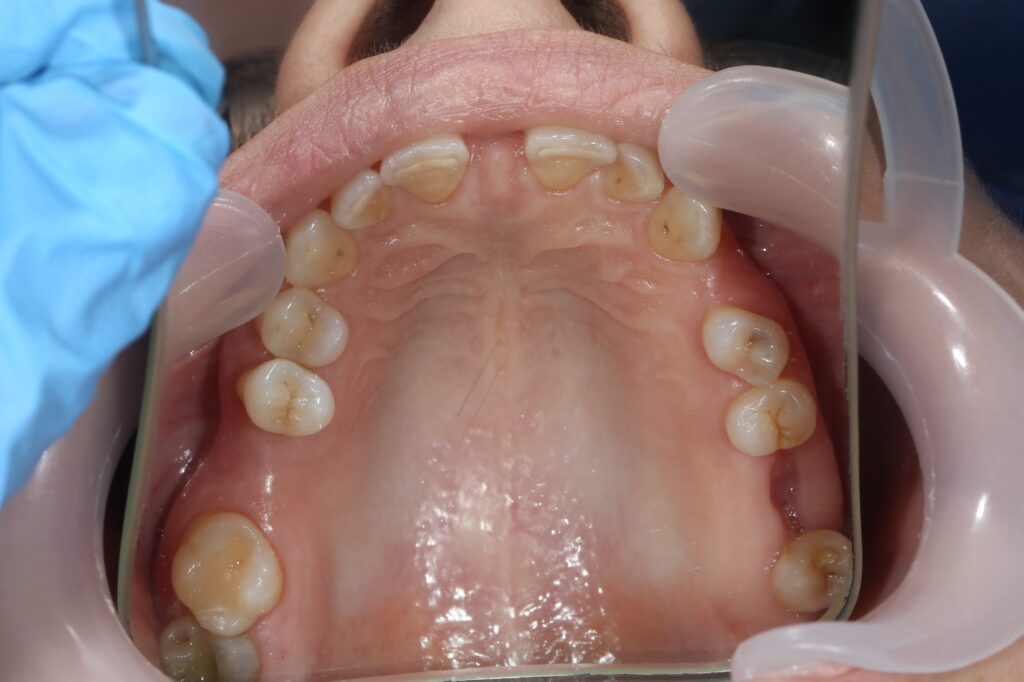

Результаты ортодонтической части

Была установлена брекет-система Damon Q. Срок лечения брекетами составил 11 месяцев.